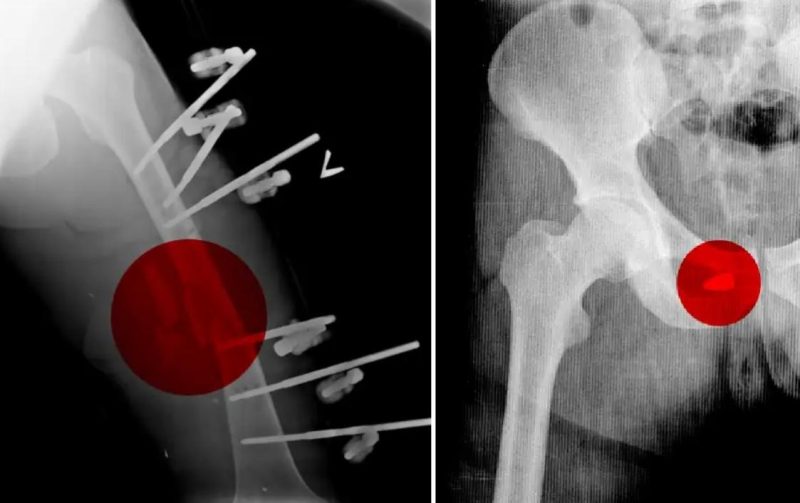

Тем не менее Андрею удалось тайно сделать копии рентгеновских снимков десятков военнослужащих, проходивших лечение в Мозырской городской больнице. На сканах были указаны имена и возраст солдат, многим из которых было от 19 до 21 года.

По его словам, самая большая партия раненых прибыла в Мозырскую больницу рано утром 28 февраля: российские солдаты вносили их внутрь на носилках и оставляли у входных дверей. Врачи быстро оценивали состояние поступивших и сортировали в порядке приоритета оказания помощи, нанося на лоб цифры от 1 до 3. Всего в тот день привезли более 100 российских военнослужащих с различными ранениями и травмами, сложными переломами от взрывов и обстрелов.

У одних отсутствовали глаза, другим требовалась ампутация. Прибыли с гангренозными, раздробленными конечностями, некоторые были парализованы, один потерял часть мозга, другой — нижнюю челюсть. Рентгеновские снимки показали, что некоторые из них были перевязаны жгутами в течение нескольких дней, чтобы остановить кровь.

Как пишет CNN, Андрей в конце марта был задержан по обвинению в коррупции [вероятно, речь идет о так называемом «деле ортопедов»], из СИЗО его отпустили в мае, а в августе он нелегально покинул Беларусь. Сейчас медик вместе с семьей находится в одной из европейских стран. Для подтверждения своих слов он предоставил копии рентгеновских снимков проходивших лечение в его больнице российских солдат.

«Генерал-майор России Сергей Нырков, получивший тяжелое ранение в живот в Чернобыле, также лечился в Мозырской больнице, судя по его рентгеновскому снимку, который был среди тех, что Андрей вывез контрабандой», — пишет CNN.